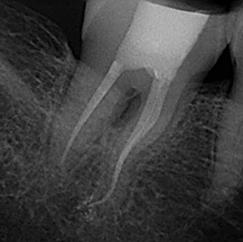

Due to the controlled memory, the files always follow the anatomy of the canal, thus significantly reducing the risk of ledging, transportation or perforation of a canal. Like stainless steel files, the HyFlex EDM files can be pre-bent.

This is a crucial advantage in extremely curved root canals to avoid the creation of steps.

Clinical Case by

Gianluca Fumei